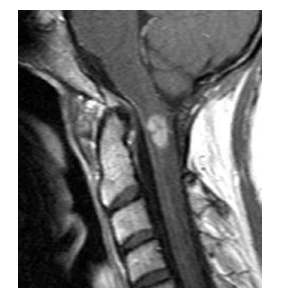

A 39-year-old presents with a 6-month history of tingling in her fingers and in the last few months, her legs. There is no bowel or bladder disturbance. On examination, there is cape-like pattern of pain and temperature loss in her upper limbs. Upper limbs are weak distally 4/5, and reflexes are globally brisk with extensor plantar responses bilaterally. MRI is shown. Which one of the following is most likely?

a—Astrocytoma

A 39-year-old presents with a 6-month history of tingling in her fingers and in the last few months, her legs. There is no bowel or bladder disturbance. On examination, there is cape-like pattern of pain and temperature loss in her upper limbs. Upper limbs are weak distally

4/5, and reflexes are globally briskwithextensor plantar responses bilaterally. MRI is shown. Which one of the following is most likely?

a. Astrocytoma

A

Astrocytomas are the second most common intramedullary spinal cord tumors in adults (30%),

compared to children in which they are the commonest. Almost 60% of these tumors occur in the cervical and cervicothoracic region, and 20%

have an associated syrinx. Back pain and motor

deficits are the most common presenting symptom in astrocytomas. The most significant prognostic factors in patients with primary spinal cord

astrocytoma are tumor histology, tumor grade,

age, and performance status. Because of the rare

nature of this disease, almost all data are based

on retrospective reviews fraught with selection

bias. Therefore, neither the extent of resection

nor treatment with adjuvant irradiation appears

to be prognostic, although this is controversial.

The classic MRI appearance of intramedullary

astrocytoma is cord enlargement with a central

lesion with poorly defined margins, cysts, peritumoral edema and patchy enhancement (no

enhancement in 30%). It is typically isointense

to hypointense on T1-weighted images and

hyperintense on T2-weighted images. The treatment of choice for intramedullary astrocytomas is complete excision of the tumor, when it can be safely accomplished without neurologic compromise. Otherwise, an incomplete excision is typically performed for grade I lesions, and biopsy alone is the surgical strategy for the

non-exophytic component of an infiltrative glioma. GTR is typically extremely difficult to

achieve because of the infiltrative nature of all

but the pilocytic lesions, with most authors

reporting a 0-50% likelihood of GTR for spinal

cord astrocytoma. In patients with favorable

prognostic factors (low-grade histologic findings,

good performance status, and young age), observation with serial imaging studies, reserving irradiation for local recurrence, is an appropriate

management option, particularly for young children. Radiation should be considered for highgrade tumors, inoperable tumors, tumors remaining after surgery, and recurring tumors. In the remainder of patients, adjuvant irradiation is

usually recommended because progression of

tumor in the spinal cord may lead to significant

neurologic impairment. The overall outcomes

are similar for patients with low-grade gliomas

of the spinal cord treated either by GTR or

STR or biopsy followed by external beam irradiation (EBRT), with most series reporting OS at

5 years of 55-100%. With high-grade tumors in

adults and children, the median survival time is

quite poor (4-10 months) despite surgery and

EBRT. Extrapolating from the results of Stupp et al. for intracranial glioblastoma, temozolomide

has emerged as a treatment strategy in high-grade

intramedullary tumors